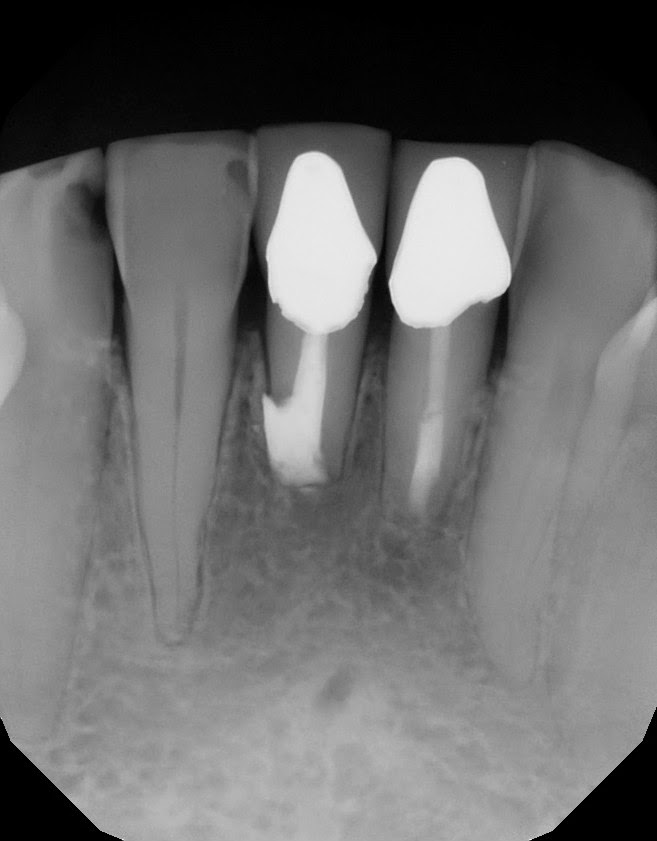

This patient came to Superstition Springs Endodontics in 2012. She reported trauma in the early 1970's - when one of her kids accidentally head butted those teeth. They became infected and a RCT was done in the early 70's. Original crowns still in place. Her dentists ever since have pointed out the radiolucency, but for the most part is has been mostly asymptomatic. Our exam finds #24 and #25 with mild percussion sensitivity, normal probings and class II+ mobility. We discussed the resorption that appears to have affected the apex of #25. We discussed options and she wanted to try to retain the tooth, so we decided to attempt an apicoectomy with guarded prognosis.

PreOp #24 and #25 - RCT done about 40 years earlier.